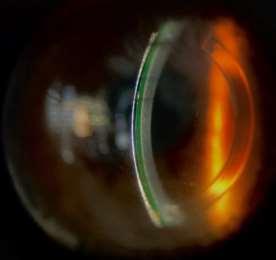

La evaluación biomicroscópica del lente mini escleral OneFit, revela una disminución del clearance especialmente inferior-, y genera un peligroso acercamiento al anillo implantado que puede afectar la comodidad y la fisiología corneal. Para corregir esto, se reduce la curva base para aumentar la profundidad de la bóveda sagital en 200 micras, y se opta por un perfil oblato del ápice del lente para acercar su cara posterior al centro corneal, con lo que se reduce el clearance central en esta zona, se provee mayor comodidad, y se minimiza la sobrecorrección negativa por compensación del menisco lagrimal; una vez transcurrido el tiempo de asentamiento del lente se procedió a evaluar la sobrerrefracción final y la zona periférica, como sigue a continuación:

Figura 14. Aspecto de la adaptación de lentes minisclerales OneFittras unahora de usocontinuo, en vista lateral del ojo derecho e izquierdo en forma respectiva.

La cronología del lente de prueba mini escleral inició después de la primera hora de uso, y se centró específicamente en la observación de cambios en el clearance, zona media limbal y zona de apoyo; el lente se mantuvo puesto por una hora adicional -completando dos en total-, y se evaluaron de nuevo los mismos parámetros para finalmente aplicar los ajustes paramétricos que se consideraron necesarios para la adaptación final, como se indica a continuación: En el ojo derecho se aumentó la altura sagital de la bóveda en 100 micras y se seleccionó el diseño oblato para reducir el clearance en la zona central; en la zona media limbal y limbal no se aplicaron cambios; mientras que en la zona de apoyo se estrecharon los bordes para lograr mejor zona de aterrizaje. En el ojo izquierdo se redujeron 50 micras al clearance; la zona media limbal y limbal no experimentó cambios; mientras que en la zona de apoyo se estrecharon los bordes para mejorar su zona de aterrizaje; en cuanto a la sobre refracción y agudeza visual resultante tras el periodo de prueba adaptativa de los lentes esclerales puestos, se lograron los siguientes valores: